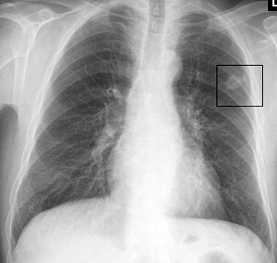

Рентгенография при раке легкого выявляет округлую тень слева. С целью дифференциальной диагностики (отличить рак легкого от туберкуломы, кисты или пневмонии) необходимо выполнять компьютерную томографию — КТ.

Прямым показанием к проведению КТ служит обнаружение при флюорогрофическом исследовании или при рентгенографии четко очаговой тени на снимке. Конечно, рак легких на рентгене выглядит не очень специфично - ведь похожие изменения могут быть обусловлены также туберкулезом, другими доброкачественными опухолями, и даже пневмонией. Все эти состояния могут быть дифференцированы с помощью КТ.